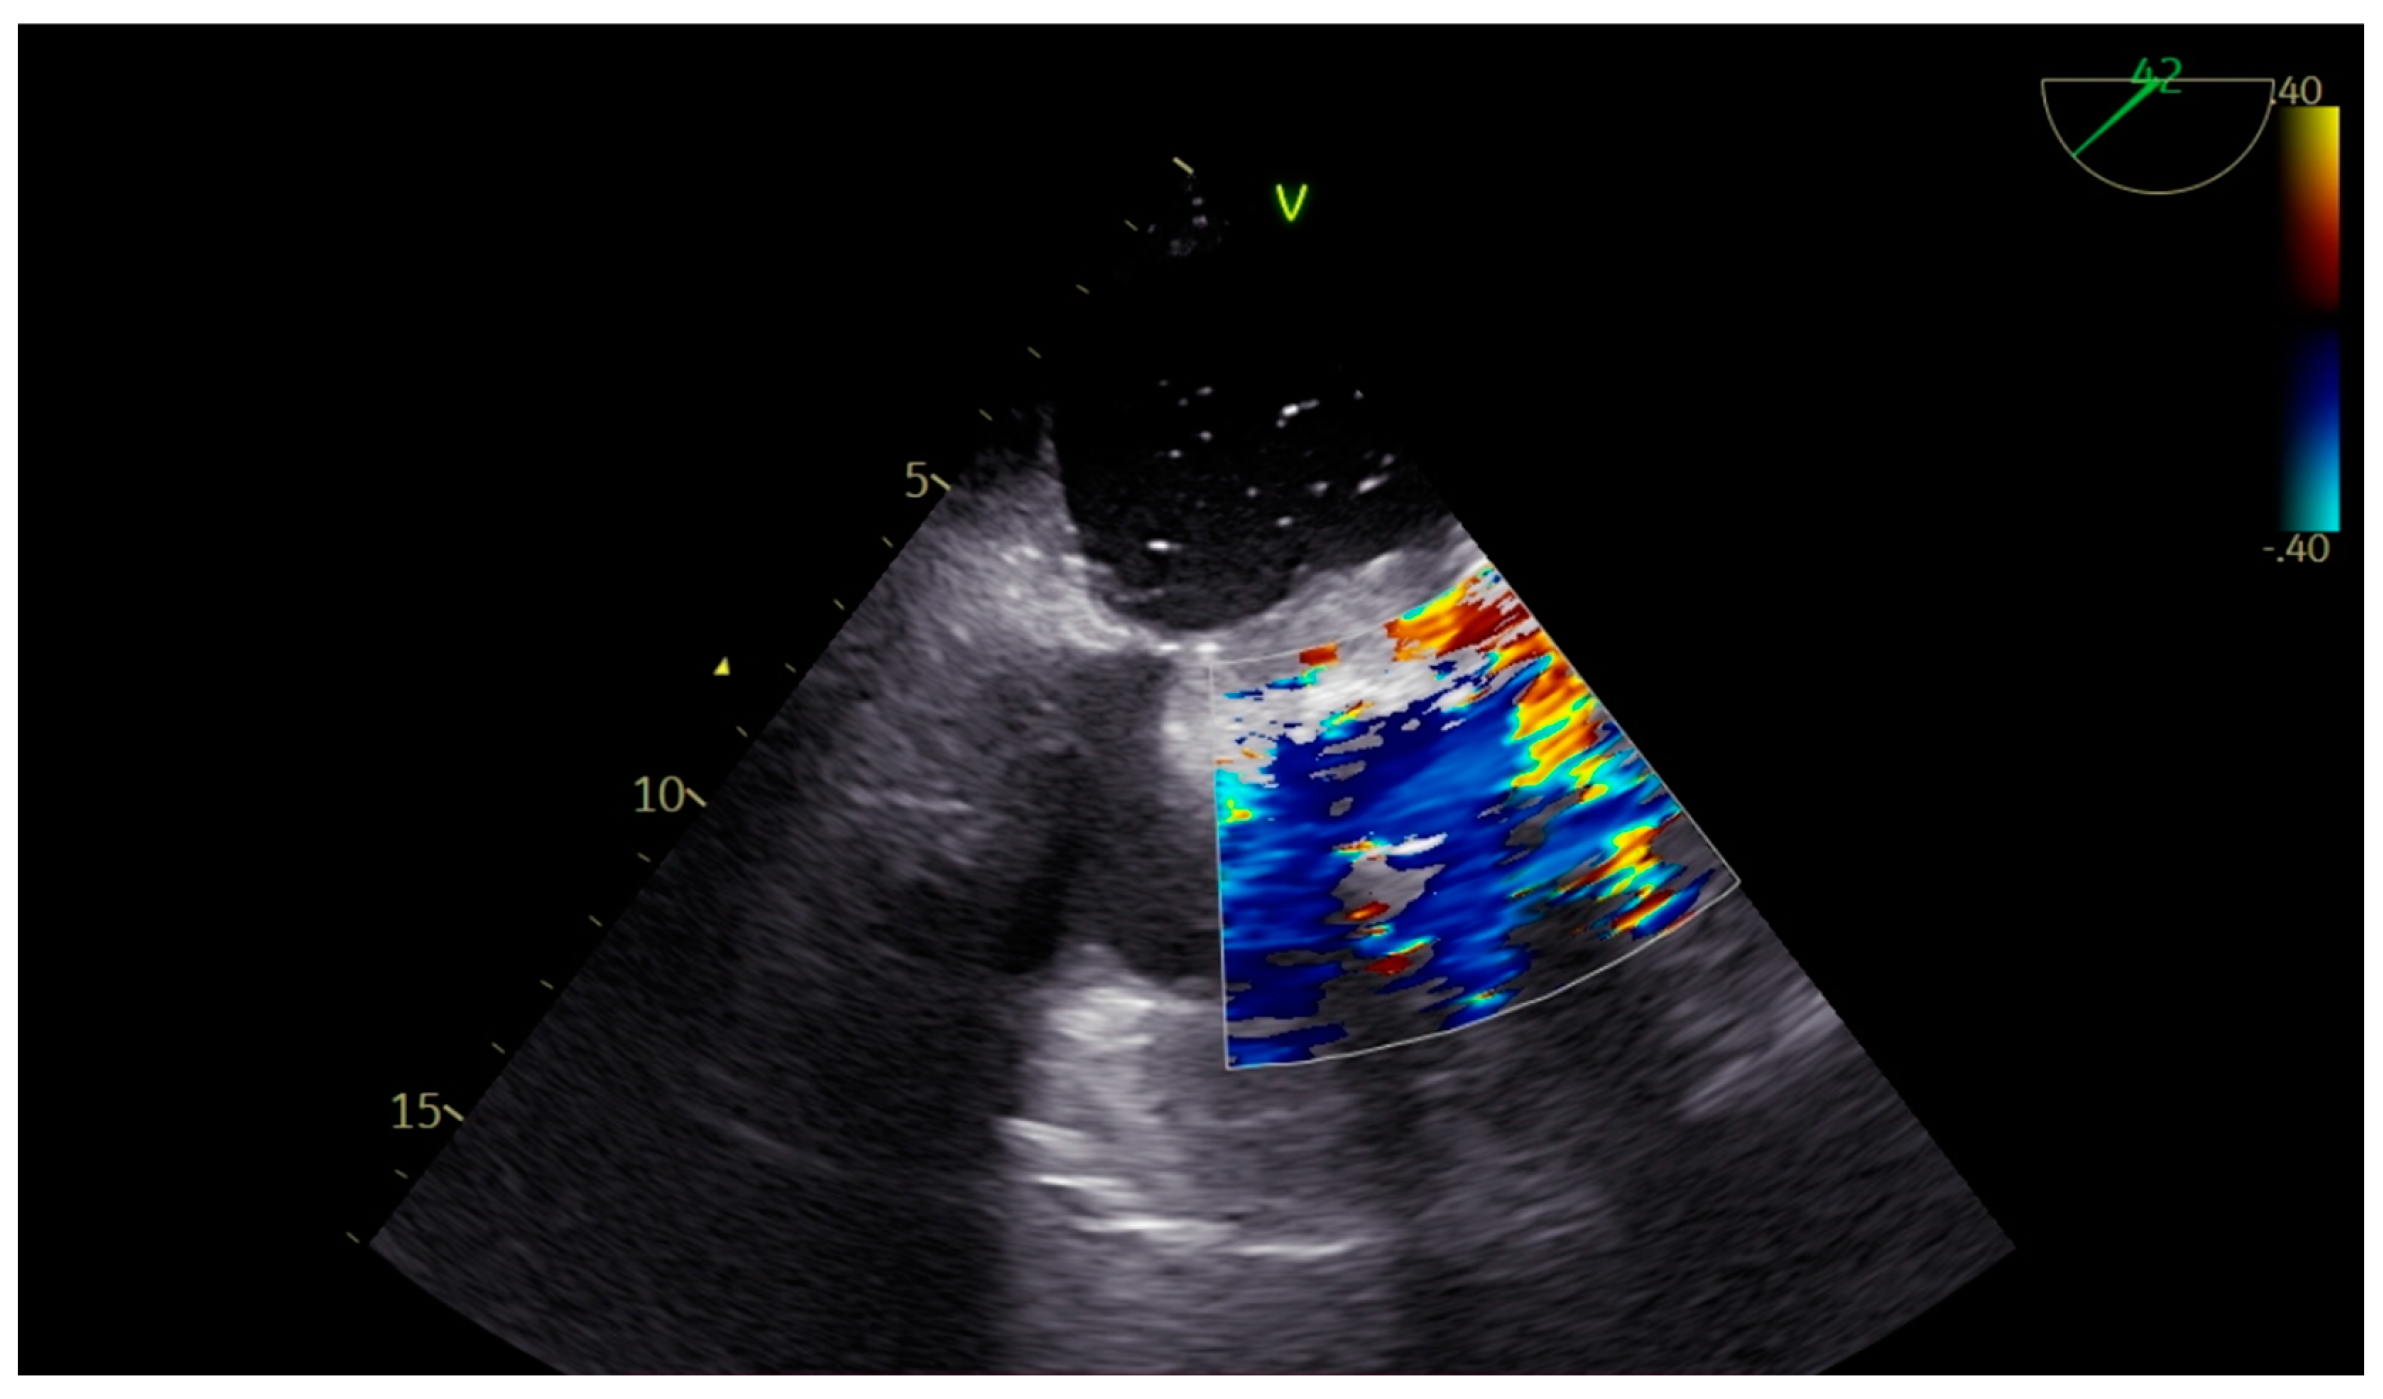

Left Atrial Dissection After Mitral and Aortic Valve Replacement: The Importance of Early Diagnosis of a Rare Entity

2. Case Presentation